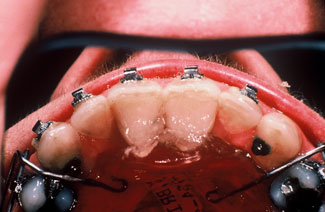

Intra-oral photo of patient pre-treatment shows severe Class II, division 1 occlusion with loss of interdental height.

Lingual shelf augmented with removable appliance with inclined plane.